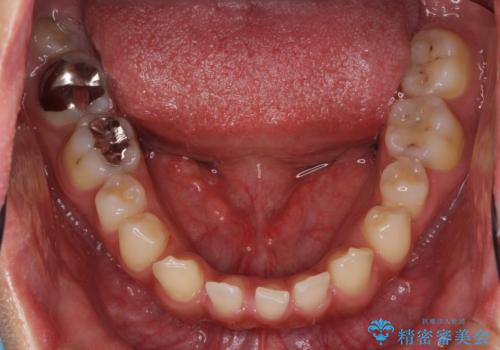

歯の位置が悪く、隙間も大きいためセラミックで被せても到底思ったような仕上がりにならないこと、下の歯が咬み込んでいるためセラミックはおろか前歯が短期間で折れてしまうリスクが非常に高いことを説明しました。

上はインビザラインで目立たないように前歯を下げ、下は難しいため、ワイヤー矯正で咬み込んでいる下の歯を沈める処置を初め行いました。最終的には上下ともインビザライン矯正で仕上げました。

下の前歯が生まれつき1本少なかったため、その部分には最終的にインプラントを入れ、下の歯が下がりすぎないようにかつ上の前歯にしっかり咬むように仕上げました。